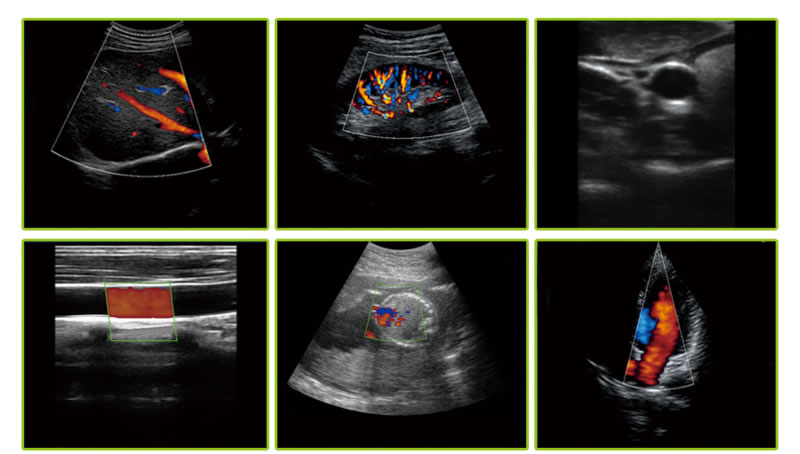

-成像模式: B, B/M, B+Color, B+PDI, B+PW

-探头类型:凸阵、微凸、线阵、窄头线阵、腔内、相控阵(即将推出),有单头探头,也有上述种类任意2个组合成的双头探头

凸阵 3.5MHz/5MHz, 90/160/220/305mm, 60°

线阵 7.5MHz/10MHz, 20/40/60/100mm, 40mm

窄头线阵 10MHz/14MHz, 20/30/40/55mm, 25mm

微凸 3.5MHz/5MHz, 90/130/160/200mm, 88°

腔内 6.5MHz/8MHz, 40/60/80/100mm, 149°